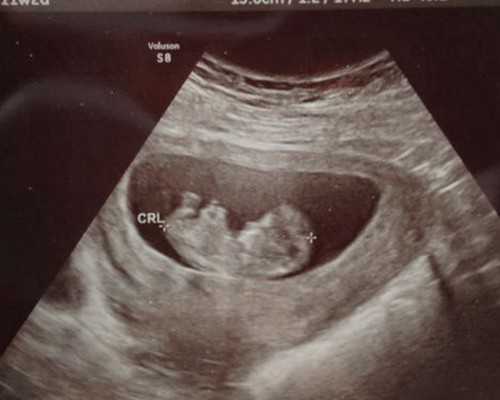

我们传统的检测胎儿性别的方式想必大家都是非常熟悉的,在这众多的检测方式当中大家最为熟悉的肯定是B超鉴定了,但是这个B超的检测方式最主要的还是需要医生通过仪器去观察孕妈妈腹中胎儿的变化,随后再去结合自己以往的经验从而得知一些想要的结果。

准妈妈只需要经B超确认怀孕满6周(胚芽长3mm),胎儿胎心可见,即可以做这个检测。香港查男女为合法,也是目前检测宝宝性别最早、最安全、最科学、最权威的方法。准确率可达99.99%以上

1、最早:在B超确认胎儿满6周以上,并胎心可见,胚芽长3mm就可进行鉴定,让准父母可以最早为宝宝做准备;

而早期的性别检测在香港已经相当的成熟,香港无创胎儿性别鉴定,也叫香港验血检测。只要在B超的确认下胎龄达到6周就可以检测了。是通过抽取母体血检测,通过验证该DNA片段是否存在Y染色体来判断男女的,属于非侵入性方法,对宝宝和妈妈都没有任何伤害。准确率99.8%,是目前最受欢迎的鉴定方法。

传统的产前诊断方法(羊膜穿刺术、绒毛采检术、B超)需要怀孕周期比较长,并对孕妇和胎儿均具有一定的创伤,可导致1%-5%的流产率,我们一般不提倡。

近几年,孕妇血中存在着胎儿细胞和胎儿DNA已是不争的事实,可利用DNA母体血液鉴定宝宝男女。香港验血检测采用母血样本提取母体血浆或血清中的胎儿DNA进行胎儿性别鉴定成为研究的热点,在国外和香港都已很成熟,孕周满6周就可以进行Y-DNA检测。